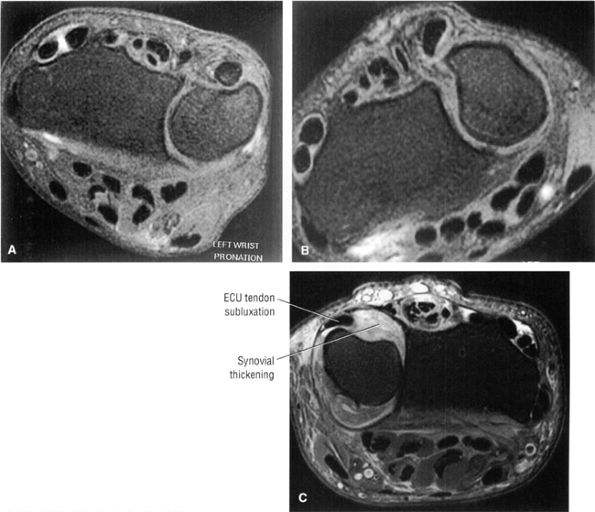

FIGURE 10.15 ● EXTENSOR CARPI ULNARIS The extensor carpi ulnaris tendon extends and adducts the wrist. It is commonly affected in tendinosis and tenosynovitis as it passes through the groove on the distal ulna. Subluxation of the extensor carpi ulnaris can also occur at this location related to disruption or insufficiency of the ligament that covers the tendon in this groove. The extensor carpi ulnaris tendon subsheath is a component of the triangular fibrocartilage complex.

|